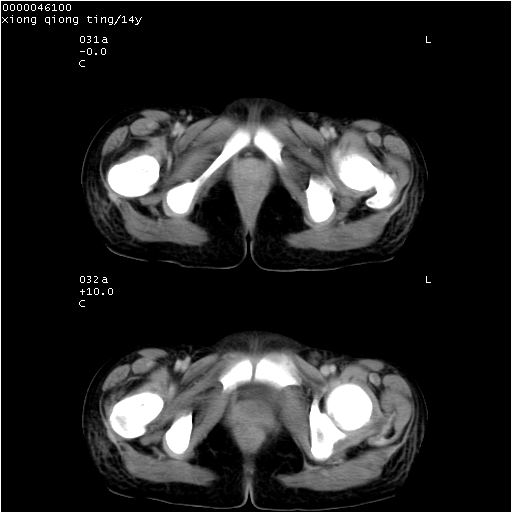

患儿 女,14岁。不规则发热一周,偶感头痛,无抽搐及呕吐。pe:神清,精神差,双侧瞳孔等大等圆,对光反射敏感,双肺未闻及明显啰音,心音有力,腹部触之似揉面感,下腹压痛,无反跳痛。

腹部b超提示:子宫缩小,盆腔积液,肝实质回声密集。

临床诊断:发热原因待查:1)腹部结核感染。2)伤寒?3)结缔组织病?

中下腹及盆腔ct轴位平扫+增强扫描(层厚10mm,螺距1.0,重建间隔10mm),图像如下:

(注:患儿检查当日上午9时口服胃肠道对比剂,下午3时许行ct扫描检查,未行对比剂直肠保留灌肠,检查当日患儿腹泻)

中下腹及盆腔ct轴位扫描(ps+ce)提示:腹部肠管明显充气扩张,并见数个不同宽度之气液平面;疑不全性肠梗阻或肠郁张。临床会诊考虑为患儿腹泻,肠郁张所致;后来未经特殊处理,患儿大便恢复正常,亦无腹胀。

临床出院诊断:1)结核性腹膜炎。2)腹膜后淋巴结结核。3)脂肪肝。